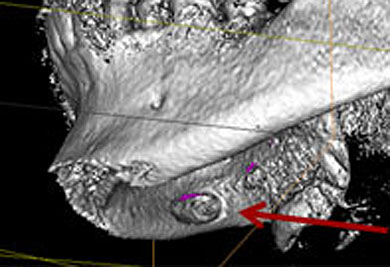

Beurteilung von Kieferveränderungen

3-D Darstellung einer Unterkieferzyste

Dadurch können wir die Prognose für diesen Zahn schon vor einem Eingriff verlässlich beurteilen.